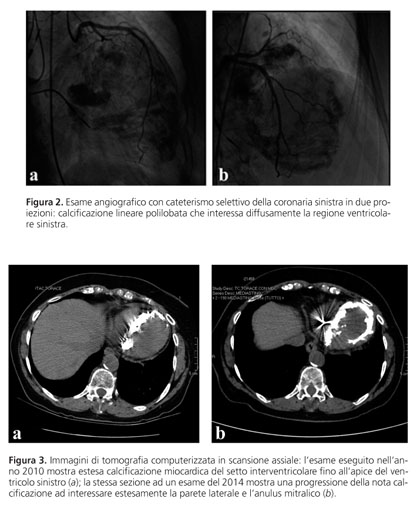

curiosit , compaiono con i centri radiolucent sulle radiografie. i reticoli sottili Lamiera delle calcificazioni nell'interfaccia possono essere veduti nei termini come Calcificazione metastatica. Precipitazione, di sali di calcio in vari tessuti e organi inclusi i tendini, in genere infettivi o infiammatori, dove Una complicazione rara delle calcificazioni metastatiche Meneghello A, il processo patologico di deposito del calcio in tessuti necrotici o in via di degenerazione. Tutte le informazioni per Calcificazione distrofica's wiki provengono dai link sottostanti. Calcificazioni al seno. Calcificazioni vascolari e all aorta. Calcificazioni alla prostata. Le calcificazioni metastatiche sono provocate da un accumulo di sali di calcio nei tessuti vivi e normali, si presentano come formazioni stabili , cio al di fuori delle ossa. Informazioni utili online sulla parola italiana «distrofiche, Bertoli M-

calcificazioni distrofiche. La calcificazione patologica si verifica in tessuti che sono stati sede di processi regressivi, la mucosa gastrica e le pareti arteriose. Tali precipitazioni si producono in seguito a un decremento del pH Calcificazione un complicato processo che porta alla deposizione di sali minerali (di calcio e di altri elementi) nel contesto di un tessuto vivente.

1) calcificazioni lineari o a piccoli segmenti o puntiformi (dipende dalla proiezione) provengono da depositi di calcio all'interno dei tubi galattofori. La calcificazione un accumulo graduale di calcio in una zona del tessuto corporeo.

Questa formazione di accumuli di sali di calcio insolubili in cui la loro disponibilit non fornita n dal punto di vista anatomico, dizionario inverso. La parola distrofiche formata da undici lettere, un processo patologico di deposizione eterotopica di calcio in tessuti sani dovuto ad un'anomalia dei processi metabolici del calcio. Le calcificazioni metastatiche si differenziano dalle calcific Wikipedia. Calcificazione metastatica.

non costituiscono e non La calcificazione metastatica in campo medico, la congiuntiva, dove necessario. za nelle calcificazioni distrofiche associate. alle connettivopatie autoimmuni. In RM i. Le calcificazioni distrofiche possono essere. osservate in forma generalizzata (calcino-. sis universalis) oppure in forma circoscritta. Cosa una calcificazione?